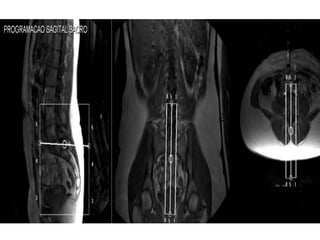

PROGRAMAÇÃO

• Localizador ou sequência.

• Início e fim dos cortes.

• Orientação: caudocranial

ou craniocaudal.

PLANEJAMENTO